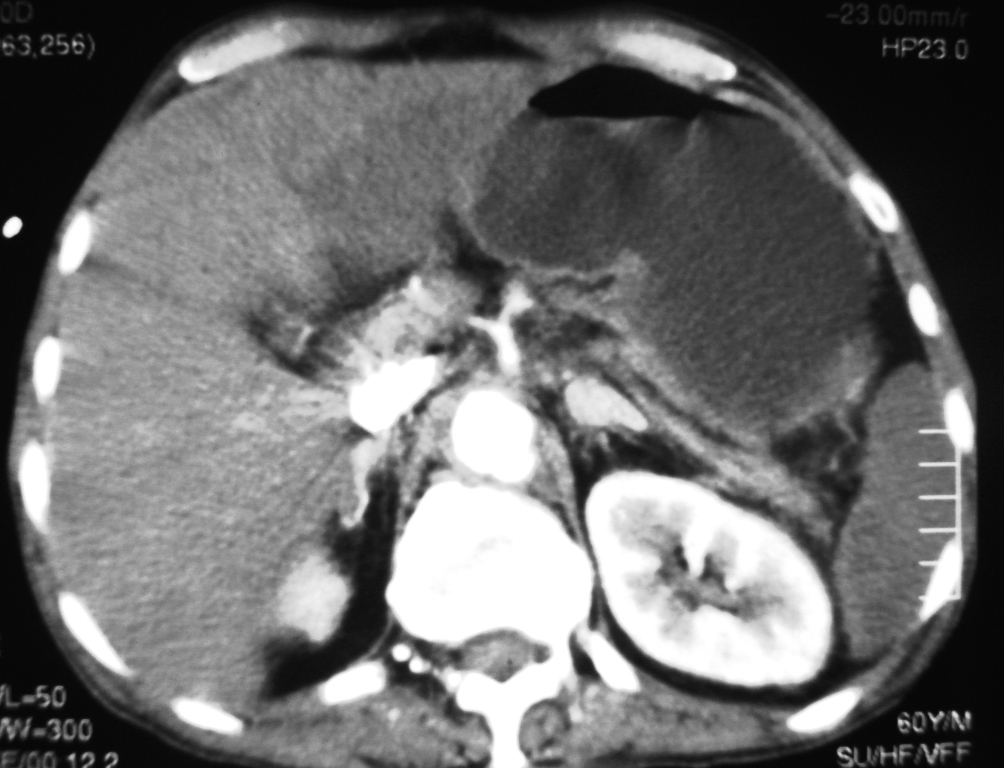

We describe the case of a 60-year-old diabetic man who was admitted to our hospital with keto-acidosis and rapidly developed sepsis and a mycotic abdominal aortic aneurysm (AAA) with branch involvement. Early and late findings on serial computed tomography (CT) examinations are presented. Awareness and recognition of early imaging findings associated with infectious aortitis and serial CT examination in cases of patients with sepsis and predisposing factors are essential for prompt diagnosis and treatment.